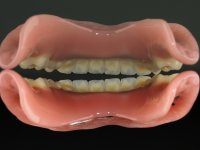

After the implant impressions with silicones, the working model was built with artificial gingiva. Then, the dental technician fabricates the record bases with the wax rims with the particularity of being screwed on the implants to achieve a proper stability. The correct vertical dimension and the lip support were determined with record bases screwed over the implants. To validate these records we have also used the “Individualized Geometric Analysis of Facial Harmony (AGIHF)” by Professor Carlos Silva.

Then, the teeth were mounted in the screwed record bases and function and aesthetics were clinically evaluated. After these evaluations, the dental technician develops silicone walls that guide the fabrication of the milled bars. The precise passive fit of the bars was checked clinically and with radiographs. Then, a pick-up impression with an individualized tray was done to achieve a functional impression of the soft-tissues.